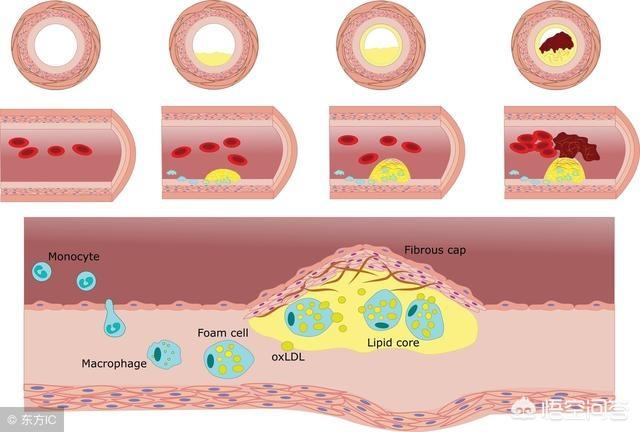

Sous l'influence de facteurs de risque cardiovasculaire tels que l'hyperlipidémie, la paroi interne des vaisseaux sanguins est progressivement endommagée et les lipides en excès dans le sang se déposent progressivement sous la paroi du vaisseau, formant un noyau lipidique athéromateux jaune, et finalement une chape fibreuse se forme dans le noyau lipidique, ce qui constitue le processus de formation de la plaque artérielle. La plaque est un facteur de risque conduisant à l'athérosclérose, et les plaques qui ont des problèmes de stabilité et se rompent peuvent conduire à une agrégation plaquettaire réactive. L'agrégation réactive des plaquettes peut même conduire à la formation de caillots sanguins, bloquant les vaisseaux artériels et provoquant des maladies cardiovasculaires infarciques. Ce qu'il faut faire, c'est prévenir la formation de la plaque par des médicaments et des exercices raisonnables, essayer de maintenir la stabilité de la plaque existante, ralentir le processus d'athérosclérose et empêcher la rupture de la plaque d'entraîner un risque plus élevé.

La plaque a la plaque veineuse, la plaque artérielle, c'est dans le rôle de multiples facteurs étiologiques, en raison de la lipidation de la précipitation, pour dire les choses franchement, c'est-à-dire, vous graissez plus, la digestion et l'utilisation ne peut pas être, dans les lipides sanguins quatre et d'autres facteurs multiples sous l'influence de et puis des dommages à l'intima, le dépôt à la couche interne des vaisseaux sanguins, la formation d'un noyau lipidique jaune athéromateux, et finalement dans la formation d'un noyau fibreux sur le noyau lipidique, qui est normalement très stable, si la coiffe fibreuse est soumise à une inflammation soutenue. la chape fibreuse se rompt, la plaque s'écoule et les plaquettes sanguines dans le mariage éclair donnent naissance à un enfant perturbateur, appelé thrombus, qui se promène pour semer le trouble, se spécialise dans les mauvaises actions pour bloquer les vaisseaux sanguins, le thrombus dans la lumière des vaisseaux sanguins devient plus étroit en même temps, mais aussi se rompt, déclenchant des événements vasculaires cardio-cérébraux et cérébraux aigus, tels que l'accident vasculaire cérébral, l'infarctus du myocarde, l'embolie pulmonaire, l'insuffisance rénale, les veines variqueuses, etc. etc. Par conséquent, l'élimination de la plaque ne permet pas seulement de déboucher les vaisseaux sanguins, mais aussi de prévenir les accidents cardiovasculaires et cérébrovasculaires aigus, ce qui est dans l'esprit de tout le monde.

La plaque artérielle est une série de réactions inflammatoires déclenchées par des lésions de la paroi artérielle sous l'effet de multiples facteurs étiologiques, avec la formation ultérieure d'une plaque athéromateuse secondaire. La formation de la plaque est plus nocive pour le corps humain, elle rétrécit la lumière du vaisseau sanguin en même temps, elle peut aussi se rompre, déclenchant des événements cardiovasculaires aigus, par conséquent, l'élimination de la plaque non seulement débouche le vaisseau sanguin, mais prévient également les événements cardiovasculaires aigus, qui sont le battement de cœur de tous les patients. Pour le traitement de la plaque, nous pouvons commencer par la cause de la maladie, comme le contrôle des lipides sanguins, de la tension artérielle, de la glycémie, etc., ainsi que le changement d'un mauvais mode de vie, comme un régime pauvre en sel et en cholestérol, l'augmentation de l'exercice, l'arrêt du tabac et la limitation de l'alcool, etc. ou, en plus du traitement ci-dessus, nous pouvons donner des médicaments, et le choix du médicament est la statine, comme l'atorvastatine, la reserpulvastatine et ainsi de suite sont couramment utilisés dans le traitement des plaques d'athérome, et le choix exact du traitement doit être formulé sous la direction d'un médecin spécialiste. Le choix exact du traitement doit être formulé sous la direction d'un médecin spécialiste. Le plan de traitement spécifique doit être formulé sous la direction de médecins spécialistes.

La plaque est une manifestation de l'athérosclérose qui se produit dans les vaisseaux sanguins. Il existe un processus graduel de développement de la plaque qui ne se produit pas du jour au lendemain, il existe un certain mécanisme d'apparition, et l'effet thérapeutique obtenu après des interventions appropriées à différents stades du processus sera également différent, de sorte que la possibilité d'éliminer la plaque dépend du stade auquel elle se trouve.

Le processus de formation de la plaque passe par plusieurs étapes : tout d'abord, l'endothélium du vaisseau sanguin est endommagé, comme si la couche protectrice de la surface interne du vaisseau sanguin était "brisée" ; les macromolécules de graisses présentes dans le sang sont transportées par une sorte de substance appelée lipoprotéine de basse densité dans la couche intima-média de la paroi du vaisseau sanguin, où elles s'accumulent en grandes quantités ; la paroi du vaisseau sanguin s'épaissit et le traitement médical consiste à épaissir la couche intima-média de plus d'un millimètre, ce qui est considéré comme de l'athérosclérose. Lorsque l'épaississement de la couche intima-média dépasse 1 mm, on parle d'athérosclérose, telle que l'agrégation locale en une masse, c'est-à-dire la plaque précoce.

Au début de la formation de la plaque, l'accumulation de graisse provoque une série de réactions inflammatoires ; en fait, la graisse est constamment oxydée, dénaturée et forme des substances ressemblant à de la bouillie ; ces substances détruisent la structure normale des vaisseaux sanguins et deviennent partie intégrante des vaisseaux sanguins ; à ce moment-là, la matière lipidique est principalement à l'état liquide, ce que l'on appelle généralement des taches molles.

La matière lipidique d'un point faible peut se nécroser avec le temps, tout comme une infection cutanée devient fibrotique et croûteuse lorsqu'elle se remplit de pus, ou la calcification se produit lorsqu'il y a des dépôts de calcium, que la plaque se durcit et que la fonction vasoconstrictrice des vaisseaux sanguins est davantage compromise ; ces plaques sont appelées des points durs.

Les plaques précoces peuvent ne pas avoir gravement endommagé la structure des vaisseaux sanguins et il est possible qu'elles puissent être éliminées et inversées, tandis que les plaques molles et les plaques dures ont déjà remplacé la structure normale des vaisseaux sanguins. Il est impossible de les éliminer complètement, et ce qu'il faut faire, c'est arrêter et ralentir la croissance continue des plaques.